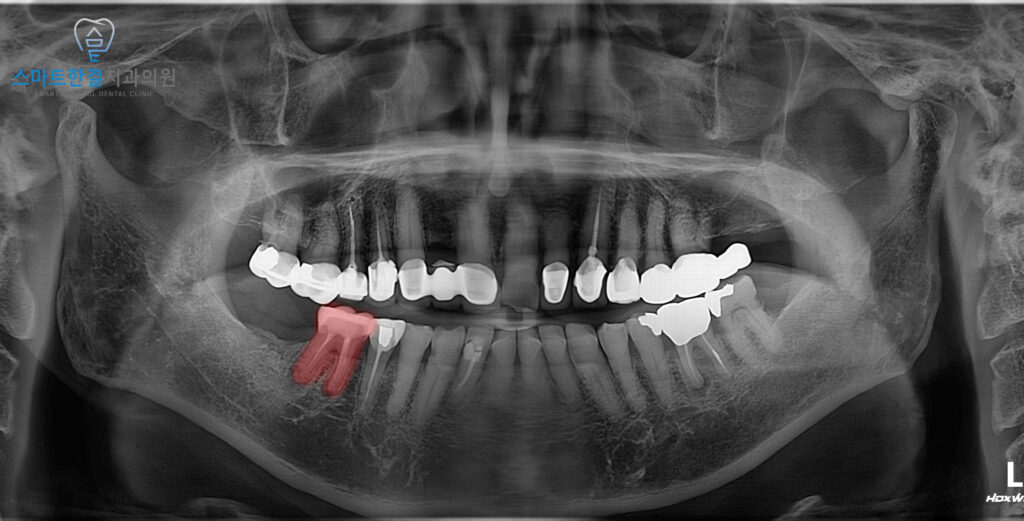

위 환자분께서는

식사를 하시거나 치아가 닿을 때마다

오른쪽 아래 치아에 통증이 느껴진다며

내원하셨어요.

확인해 보니,

통증이 발생한 부위는

이미 신경치료와 보철치료가

완료된 치아로 확인되었는데요.

겉으로 보기에는 큰 문제가 없어 보였지만,

엑스레이 촬영 결과

치아 뿌리 끝 부위에

염증이 형성된 것이 확인되었는데요.

이러한 염증은 이전 신경치료 당시

남아 있던 세균이나 미세 균열을 통해

감염이 재발하면서 생길 수 있어요.